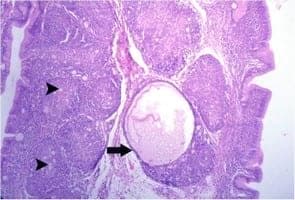

Liver of Eimeria-aflatoxin-treated group showed severe diffuse hepatocytic vacuolation (Fig.1) with presence of multifocal areas of coagulative necrosis infiltrated with mononuclear cells, primarily lymphocytes (Fig.2). Hyperplasia and desquamation of the biliary epithelium with periductal fibrosis and lymphocytic cell infiltrations were noticed (Fig.3). Similar lesions were observed in liver of aflatoxintreated group but less in severity than those of previously mentioned group. Severe cecal lesions were observed in both Eimeria-treated and Eimeria-aflatoxin-treated groups. These lesions consisted of severe mucosal and submucosal congestion, edema and hemorrhage (Fig.4) as well as mononuclear cell infiltrations, chiefly lymphocytes. In addition, the mucosal epithelium showed severe diffuse degeneration, necrosis and desquamation (Fig.5) besides presence of numerous numbers of intracellular developmental stages almost schizonts (oval structure containing basophilic banana-shaped merozoites, Fig.6). Cecum of aflatoxin-treated group showed mild degenerative and necrotic changes as well as desquamation of the mucosal epithelium (Fig.7). Lymphoid organs exhibited necrotic changes in aflatoxin-treated and Eimeria-aflatoxintreated groups, but were more severe in the latter. These changes were severe diffuse lymphocytic cell necrosis and depletion giving the bursal follicle moth-eaten appearance (Fig.8). Some bursal follicles showed large cystic cavitations devoid of lymphocytes and containing faint eosinophilic necrotic debris (Fig.9). Similar lesions were seen in the thymic follicles (Fig.10) besides interfollicular congestion.